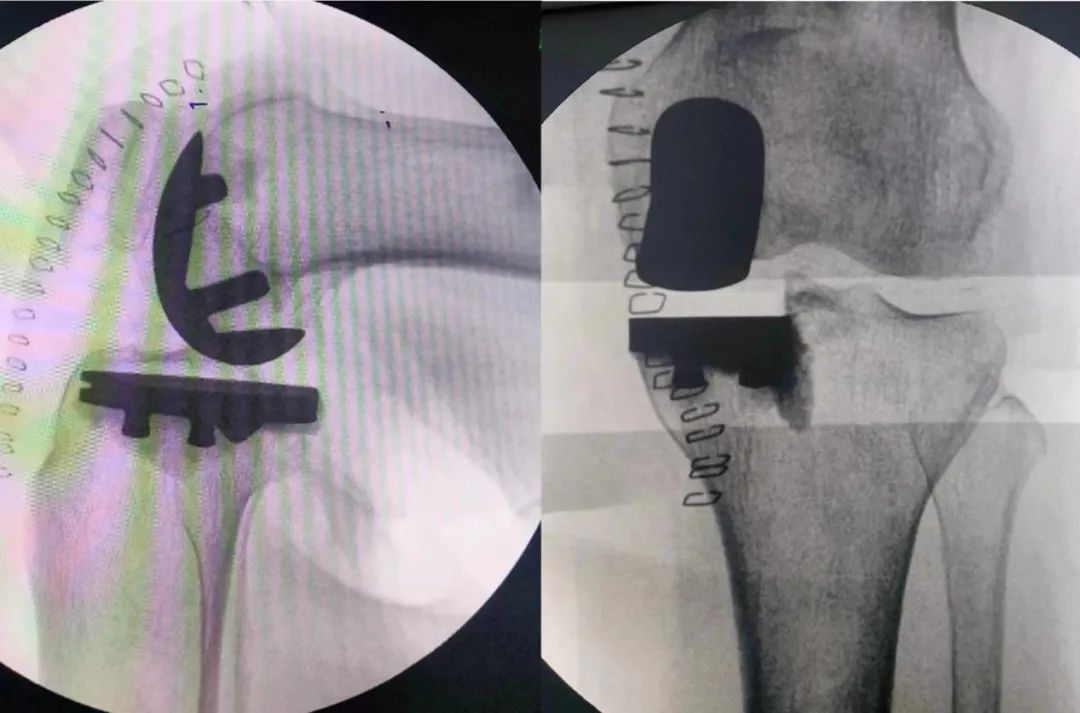

手术治疗包括:关节镜手术通过治疗关节镜清理术改善患者症状,对于膝关节力线不佳的胫股关节单间室骨关节炎,尤其是青中年且活动量较大的患者,可酌情选择胫骨高位截骨术、股骨髁上截骨术或腓骨近端截骨术,以改善关节功能并缓解疼痛。关节置换术能够显著改善重度骨关节炎的疼痛和功能。

目前膝关节置换方面,部分单间室退变的患者,如髌股关节炎、胫股关节单间室骨关节炎,在符合相应的手术指征条件下,也可以选择行相应的单间室人工关节置换手术(如上图),单间室置换能更好的保留患者本体感觉。